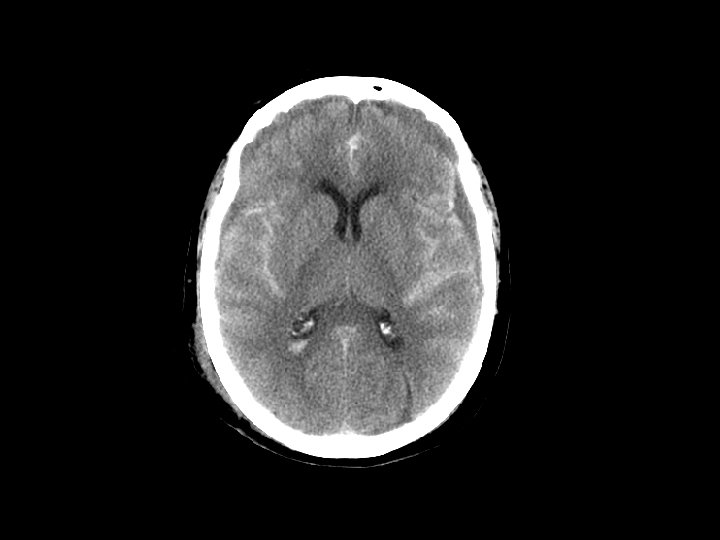

Chảy máu dưới nhện • Chảy máu dưới nhện và tụ máu là chấn thương thường gặp trên CT sau các sang chấn đụng dập • CT: xuất huyết ở các rãnh và hệ thống bể đáy • Thường kết hợp với tụ máu nội sọ • Đánh giá có thể chảy máu dưới nhện gây chấn thương (bệnh nhân xuất huyết tự nhiên và sau đó ngã) • Biến chứng: – Co thắt động mạch: 2 -3 ngày sau chấn thương